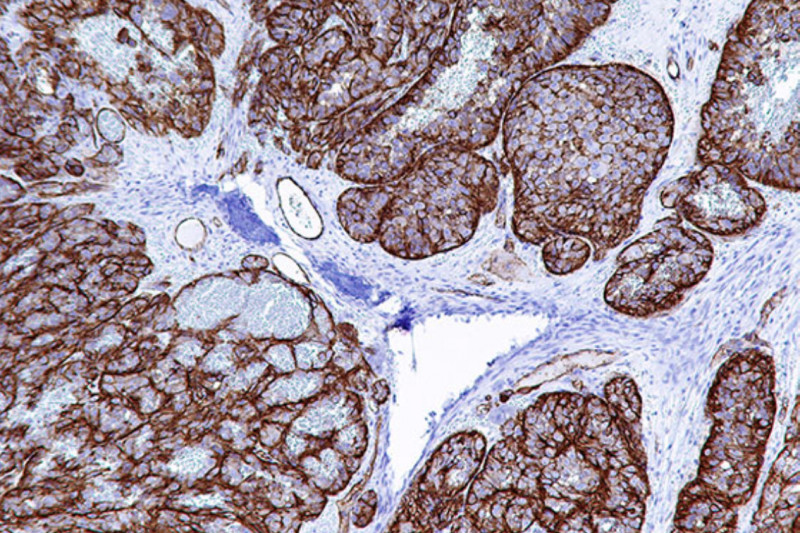

Patologia | Imuno-Histoquímica